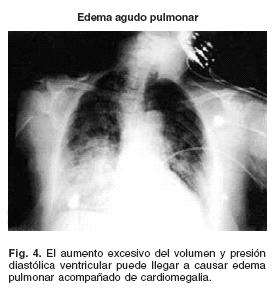

En la figura 3, se demuestra que en presencia de insuficiencia cardíaca, la curva de función ventricular se desvía hacia la derecha y abajo por lo que para un volumen diastólico normal, el gasto cardíaco estaría a tal grado reducido que sería imposible mantener una presión de perfusión tisular adecuada, esto es: estado de choque cardiogénico. La utilización del mecanismo de Starling permite normalizar el gasto cardíaco a expensas de aumentar el volumen diastólico (cardiomegalia) y con ello la presión diastólica del ventrículo izquierdo (congestión pulmonar). Recordar que el límite de este mecanismo es el edema pulmonar (Fig. 4).

B) Reserva diastólica: "Es la capacidad del corazón para aumentar el gasto cardíaco a través de mecanismo de FrankStarling, (Fig. 3) y su límite es el edema pulmonar" (Fig. 4)35

En caso de insuficiencia cardíaca, cuando la reserva cronotrópica es insuficiente para normalizar el gasto cardíaco, el aumento del volumen diastóiico, lo normaliza y ello es causa de cardiomegalia. El aumento de la precarga trae consigo aumento de la presión diastólica del ventrículo izquierdo (Figs. 3, y 5) y por consiguiente de la presión capilar pulmonar (causa disnea).19,35 Si el aumento del volumen diastóiico es excesivo, el aumento de la presión venocapilar pulmonar concomitante puede llegar a causar edema pulmonar (Fig. 4). Conviene mencionar que en la práctica clínica será necesario contar con una radiografía del tórax (cardiomegalia) o mejor de un ecocardiograma para conocer el diámetro diastólico y la fracción de expulsión; en efecto, si el volumen está aumentado y la fracción de expulsión disminuida, estaremos ante un cuadro de insuficiencia cardíaca; por el contrario si el diámetro diastólico ventricular es normal (ausencia de cardiomegalia), lo mismo que la fracción de expulsión, el cuadro será causado por disfunción diastólica ya que la precarga es normal (Fig. 5).